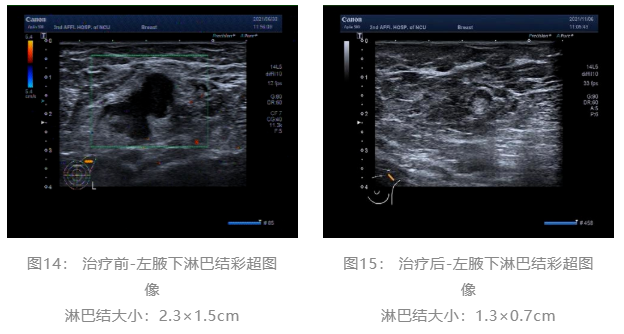

2021.06.30 乳腺彩超:左侧乳腺低回声团块,BI-RADS-US 4c类。左侧腋窝肿大淋巴结。(图1、2)

▌治疗前后影像学对比:

乳腺彩超:

术前评估:新辅助治疗期间患者无明显不适,一般状况可。新辅助治疗后左乳房肿瘤及腋下肿大淋巴结退缩明显,疗效评估PR,未发生不良事件,择期可行左乳癌改良根治术。